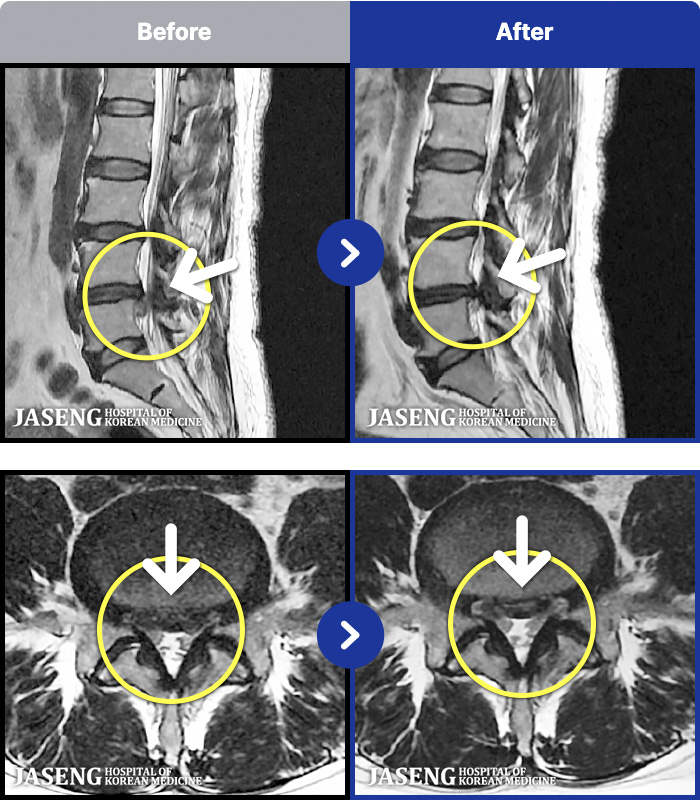

푸쉬업을 여러 번 반복한 뒤 극심한 하요부 통증 및 우측 하지부 저림

2024.03.21 ~ 2024.09.23